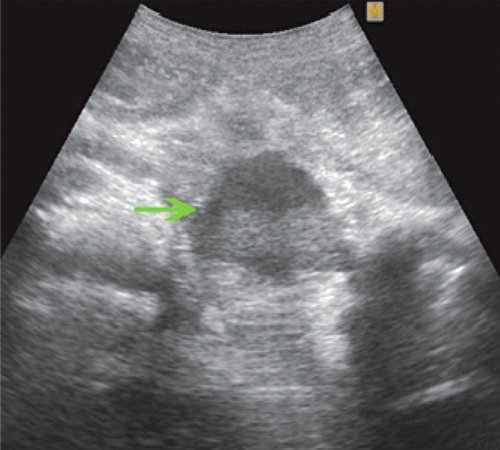

УЗИ диагностика: псевдокиста поджелудочной железы